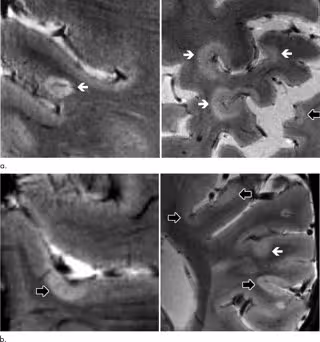

El volumen total de lesiones corticales fue un predictor de discapacidad neurológica en la evaluación inicial y de seguimiento. Los escáneres cerebrales 7T mostraron que las lesiones corticales tendían a acumularse en las marcas de la superficie del cerebro llamados surcos.

"Demostramos que los surcos corticales son las regiones donde se desarrolla la mayoría de estas lesiones --dice el doctor Mainero--. También descubrimos que estas lesiones pueden predecir la progresión de la discapacidad más que las lesiones de la materia blanca, que son las lesiones típicas de la EM que hemos estado estudiando durante años".